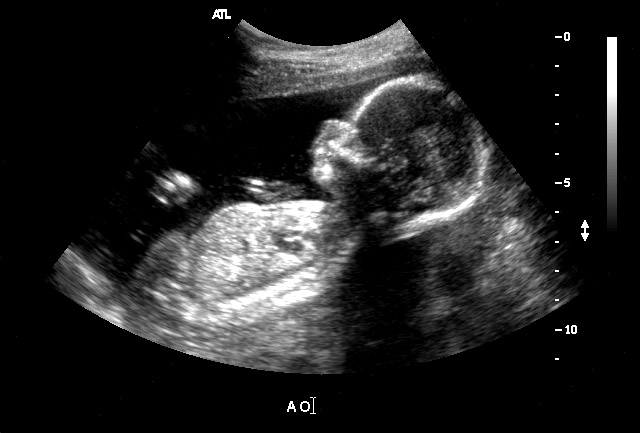

Необходимые исследования

Будущим мамам на сроке беременности 18 недель необходимо сдать кровь для тройного теста (второго пренатального скрининга), конечно же, при условии, что это не было сделано ранее. Если данное исследование даст неудовлетворительные результаты, гинеколог может направить пациентку к генетику и на УЗИ (по плану второе обязательное УЗИ проводится на сроке 20-22 недели). В ходе ультразвукового сканирования врач оценивает состоянии внутренних органов плода (они уже хорошо визуализируются), определяет, отвечают ли его размеры сроку беременности, осматривает плаценту и пуповину, проверяет маточно-плацентарный кровоток, измеряет приблизительное количество околоплодных вод, проводит контроль шейки матки и т.д.